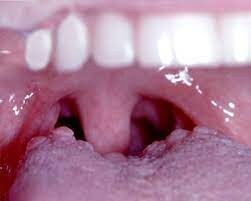

If your wisdom teeth have started to come in, you may notice that a loose flap of gum tissue has developed around them. This piece of tissue is known as an operculum, and it often develops over partially erupted teeth or teeth that do not have enough room to come in.

Learn more about issues with operculums and why they sometimes need removing.

Why Can Operculums Be a Problem?

While some operculums only partially cover a wisdom tooth, some may cover much of the chewing surface. If the flap is large, you can have an increased risk of biting the adjacent cheek tissue or the operculum itself.You can keep your enamel and attached gingiva clean with both brushing and flossing.

Operculums, on the other hand, can be difficult to keep clean since they are in the back of the mouth and because the loose tissue may trap bacteria and food debris.

If too much debris is trapped, you can develop pericoronitis, which is an inflammatory condition.  People with pericoronitis can experience bad breath, pus, and pain when eating or swallowing. If you do not treat the pericoronitis, you can experience lymph node and facial swelling.

Severe pericoronitis could lead to a complication called Ludwig's angina, where the infection spreads from the operculum to the head or neck.